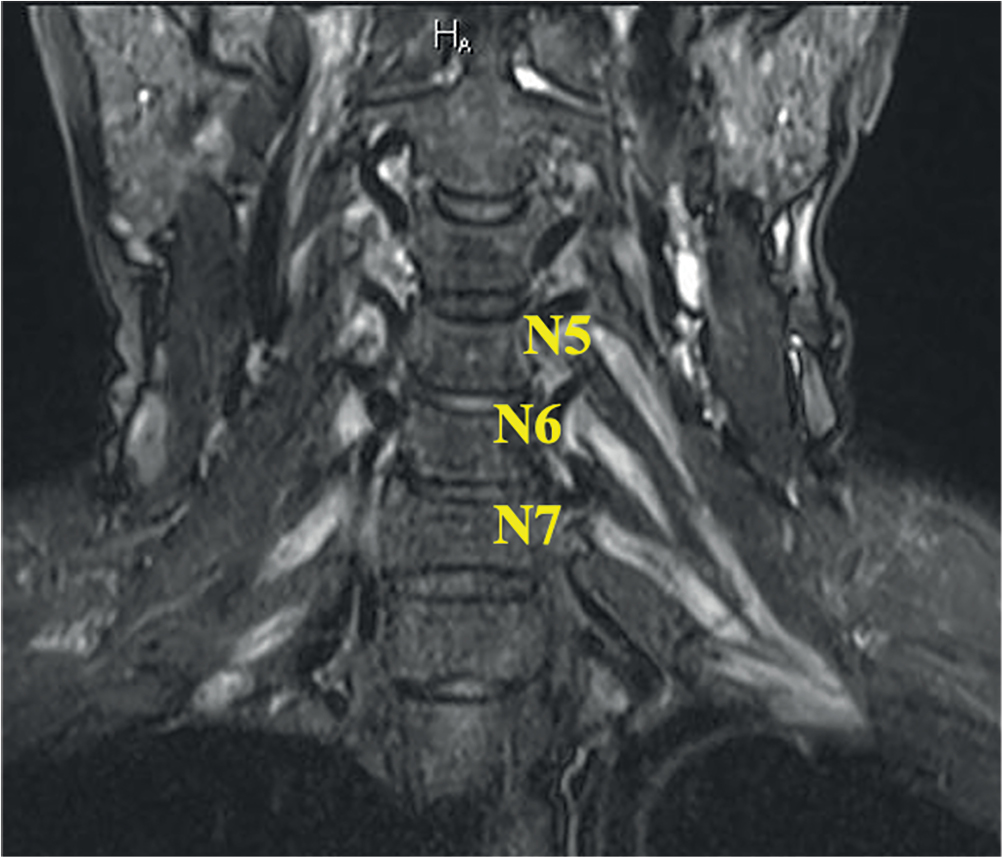

МРТ-исследование пациентов проводили на магнитно-резонансном томографе «Magnetom Siemens Prisma» с величиной индукции магнитного поля 3 Т по единому стандартному протоколу. Для оценки толщины и интенсивности МР-сигнала использовали трёхмерную последовательность STIR с высоким разрешением (TR = 3000 мс; TE = 281 мс; TI = 230 мс, размер реконструированного воксела 0,4 × 0,4 × 0,9 мм, FOV = 350 мм, количество срезов 144, длительность сканирования 7 мин 27 с). У каждого испытуемого измеряли толщину передних ветвей спинномозговых нервов на уровне C4–С7 (N5–N7) на равноудалённом расстоянии от соответствующего ганглия с обеих сторон, а также на уровне максимального утолщения; для статистического анализа использовали наибольший показатель. Кроме того, качественно оценивали интенсивность МР-сигнала от ПС на всём видимом уровне. При оценке МРТ-изображений использовали рекомендованные нормативы EAN/РNS (2021), где пороговым показателем нормальной толщины являются 5 мм в коронарном изменении. В данной работе мы представляем оценку данного параметра, опираясь на вышеупомянутый принятый на сегодняшний день единый норматив (утолщены/не утолщены). Кроме того, в режиме STIR качественно оценивали интенсивность МР-сигнала от ПС (повышена/не повышена), опираясь на опыт врача-рентгенолога, без использования количественных методик.

Рис. 3. МРТ ПС пациента с ММН (катамнез 13 лет, проводится поддерживающая терапия внутривенным иммуноглобулином в дозе 1 г/кг 1 раз в 4 нед). В режиме STIR в коронарной проекции отмечается равномерное, симметричное выраженное (до 8 мм) утолщение ПС с двух сторон, сопровождающееся повышением МР-сигнала.

Fig. 3. MRI of BPs in a MMN patient (13-year follow-up history; assessed on maintenance therapy: intravenous immunoglobulin 1 g/kg every 4 weeks). The coronal STIR MRI showed significant (≤ 8 mm) bilateral uniform symmetric BP thickening, with hyperintense signal.